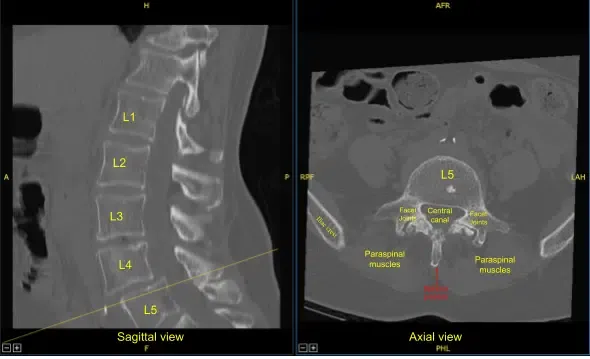

Preoperative CT of Lumbar Spine

Prior physical examination of the lumbar spine supported the diagnosis of lumbar canal stenosis. His imaging showed grade 1 to grade 2 spondylolisthesis with instability over L4-L5 with compression of nerve roots. There is also lateral recess compression at L3-L4 on the right and left side with compression of the traversing L4 nerve root.